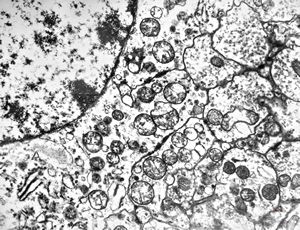

F,50y. | progressive multifocal leukoencephalopathy- viral particles in a glial cell

F,50y. | progressive multifocal leukoencephalopathy- viral particles in a glial cell

F,50y. | progressive multifocal leukoencephalopathy- viral particles in a glial cell